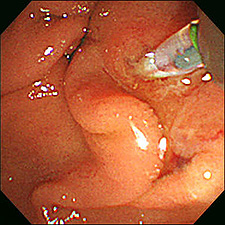

【早期胃がん】

腫瘍径約6cm

内視鏡的粘膜下層剥離術施行中